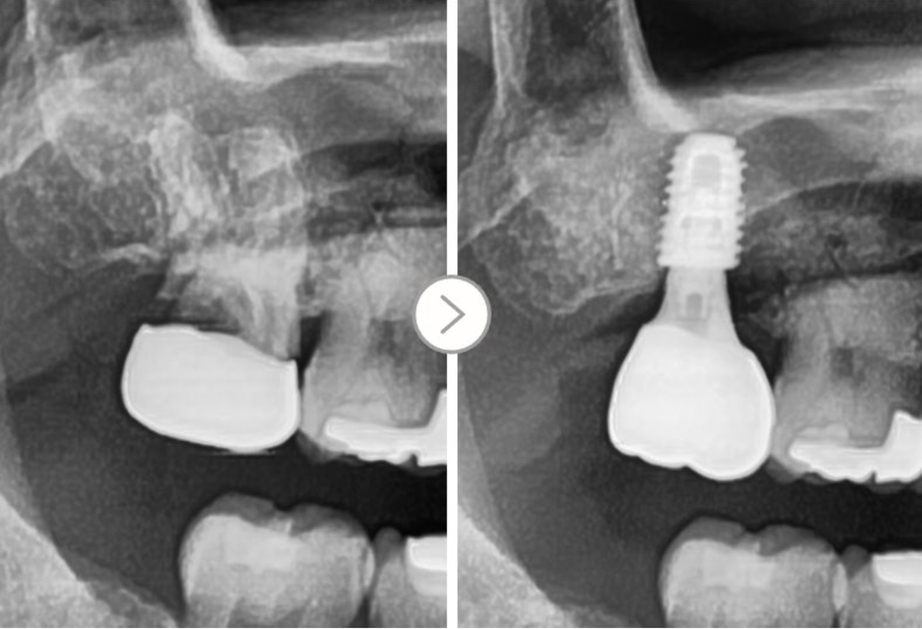

Tuy nhiên, trong trường hợp này

Vì tình trạng viêm nặng đến chân răng

▲ Viêm sâu nặng tận chân răng

Không thể phẫu thuật kéo chân răng ở trường hợp này

Điều trị cấy ghép Implant được thực hiện sau khi nhổ răng.

▲ Điều trị cấy ghép Implant sau khi nhổ răng bị sâu đến tận chân răng do mão răng cũ